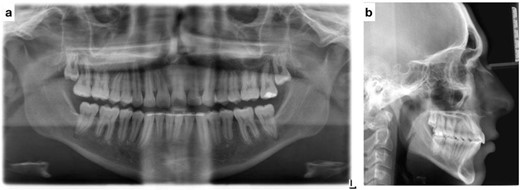

Post-treatment clinical examination showed that crowding was relieved by a 4-mm increase in the intermolar width of the maxillary and mandibular arches. In addition, a class I molar and canine relationship was achieved with good occlusion (Fig. 5) and a pleasing smile (Fig. 6). Post-treatment lateral cephalometric radiographs showed that the mandible had grown forward in the sagittal dimension, improving the skeletal profile (Fig. 7b). The upper incisors were proclined by 15° to achieve ideal labio-lingual inclination for optimum aesthetics; the lower incisor was optimally positioned to achieve ideal overjet and overbite (Fig. 7b). Mandibular anterior teeth were intruded to correct the impinging overbite and level the Curve of Spee. Finally, the patient was referred to an oral surgeon for extraction of the third molars.

Post-treatment intra-oral photos showing severe mandibular crowding

(a) Post-treatment panoramic radiograph; (b) post-treatment lateral cephalometric radiograph